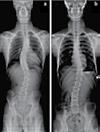

생활정보 구인, 구직, 렌트, 중고매매, 중고자동차, 레슨, 결혼, 부고 등 네줄 광고는 4주간 모두 무료입니다. 단 기업형 부동산, 사업체, 커머셜 자동차 매매 네줄 광고는 월 $30불, 모든 박스광고는 한달 $40, 이미지 삽입광고 $60 입니다. 콜로라도 타임즈 생활정보 안내는 지면과 인터넷에 게재됩니다. 척추 병원에서 풀타임 일하실 한국어 /영어 가능한 리셉션니스트 구합니다 (720) 261-4290 <060823>